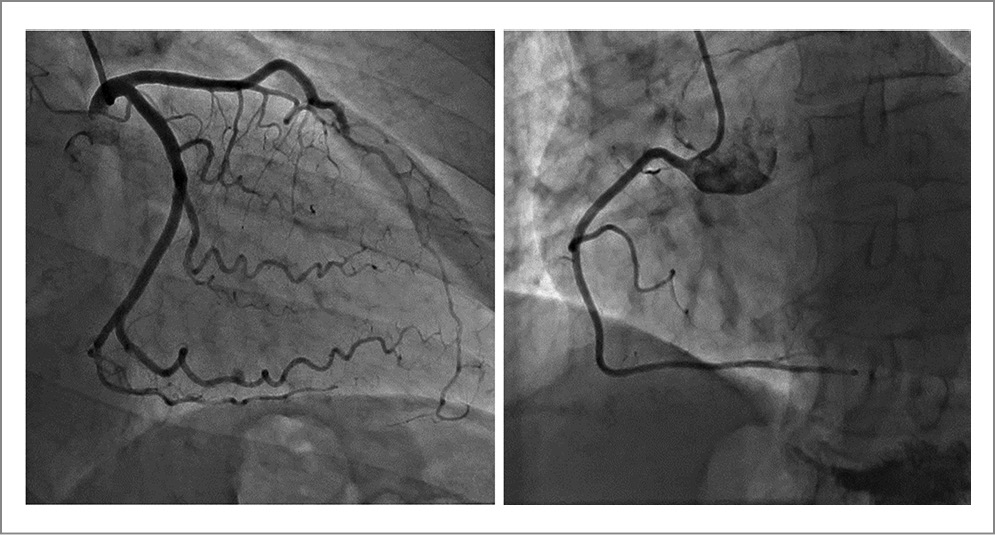

По результатам селективной КАГ – правый тип коронарного кровоснабжения, ствол левой КА обычно развит, без гемодинамически значимого стенозирования. Передняя межжелудочковая ветвь (ПМЖВ), огибающая ветвь (ОВ) и правая КА диффузно изменены на всем протяжении без гемодинамически значимого стенозирования. Отмечалось выраженное замедление антеградного кровотока, тотально по всему коронарному руслу. Syntax=0 (рис. 3).

Рис. 3. Селективная КАГ при поступлении в стационар.